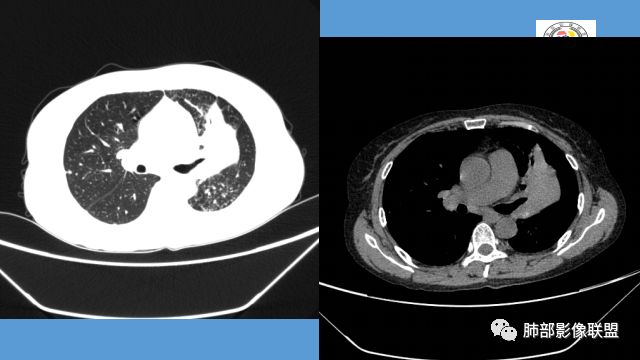

左肺团块影,形态不规则,其内见充气支气管征,增强扫描明显强化,其内见液化坏死区。下叶基底段见斑点状密度增高影。双肺门见斑点状钙化影。疾病谱有结核,增强除外了。肺癌和淋巴瘤鉴别。

病灶远端有扩张支气管,树芽,实变,纵隔肺内淋巴结钙化,考虑肺结核。

强化不是很明显,我考虑炎性病变,结核放第一位。

整个上叶尖后段阻塞性肺不张的表现,从强化来看没有异常结节状或肿块样强化,肿块内部点状钙化、纵隔多发小淋巴结、下叶背段有树芽征,整体来看支持肺结核,让人不放心的是最后一幅冠状位重建的图像尖后段支气管堵了,而且有轻度的隆起,所以很难除外粘液表皮样癌(女性,鳞癌可能性小),如果是我写报告肯定会建议纤支镜检查

中年女性,反复咳嗽咳痰4月,加重半月,咳嗽,咳黄痰。胸CT:左肺体积缩小,左肺上叶病变,病灶内可见支气管征,病灶边缘可见棘突样改变,病灶周围可见结节状卫星灶,纵隔可见淋巴结肿大,部分淋巴结可见钙化灶。增强CT病灶内可见低密度坏死区,冠状位病灶内支气管可见扩张,病灶整体呈收缩,考虑患者为良性慢性感染性病变,结核?放线?,建议支气管镜检查。

中年女性,反复咳嗽咳痰4月。胸CT:左肺上叶块状病变,病灶内可见支气管征,边缘见棘突样改变,周围可见结节状卫星灶,纵隔可见淋巴结肿大,部分淋巴结可见钙化灶。增强CT病灶内可见低密度坏死区。病灶整体呈收缩,考虑为良性病变,结核可能性大,建议支气管镜检查。

晨读:左肺上叶实变,边缘不整,部分膨隆,其内支气管有狭窄有扩张,周围小叶间隔增厚,左肺下叶背段可见气腔结节,树芽征,边缘模糊,肺门及纵膈淋巴结钙化,考虑结核。鉴别肺炎型肺癌。

1.双肺多发病灶,结节影、树丫影,边缘分布……病灶符合继发性肺结核。

2.左肺上叶大片实变影,密度不均,体积轻度增大,注意轻到中度强化及血管影未见破坏、未见坏死空洞……病灶更符合炎症,而不大支持干酪性结核及肺鳞癌等,后两者的破坏能力是比较强的。

3.支气管阻塞,沿途可见钙化及液性潴留……更符合支气管内膜结核。